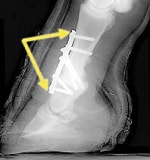

固定術・形成術

関節固定術

関節形成術

腱の形成術